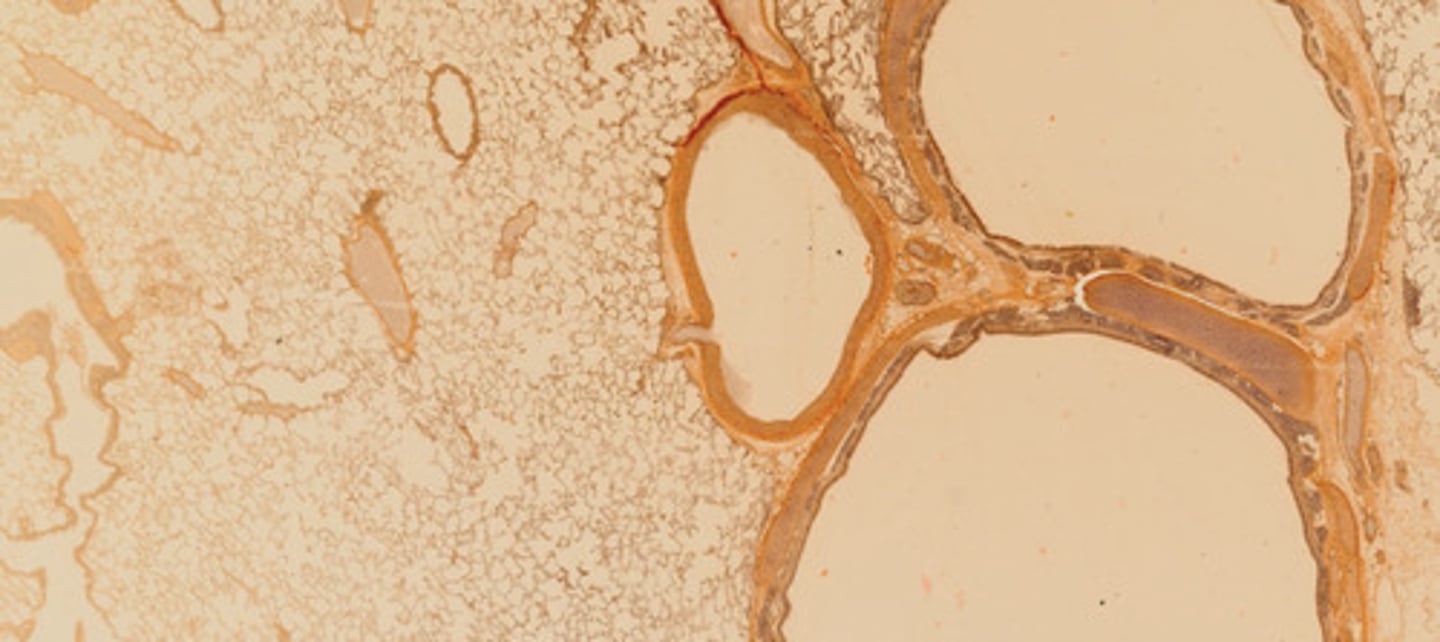

Miąższ płucny (orceina)

Tętnica typu elastycznego (rezorcyna-fuksyna)